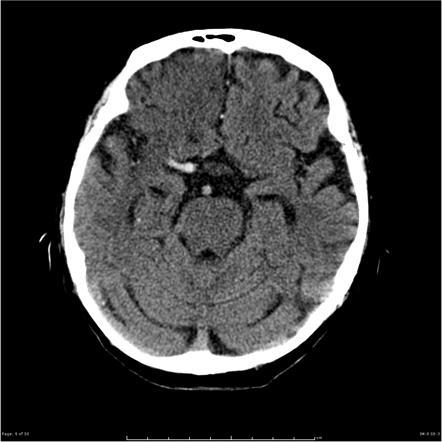

What does this CT show?

MCA ‘hyperdense artery’ sign

Indicates infarction